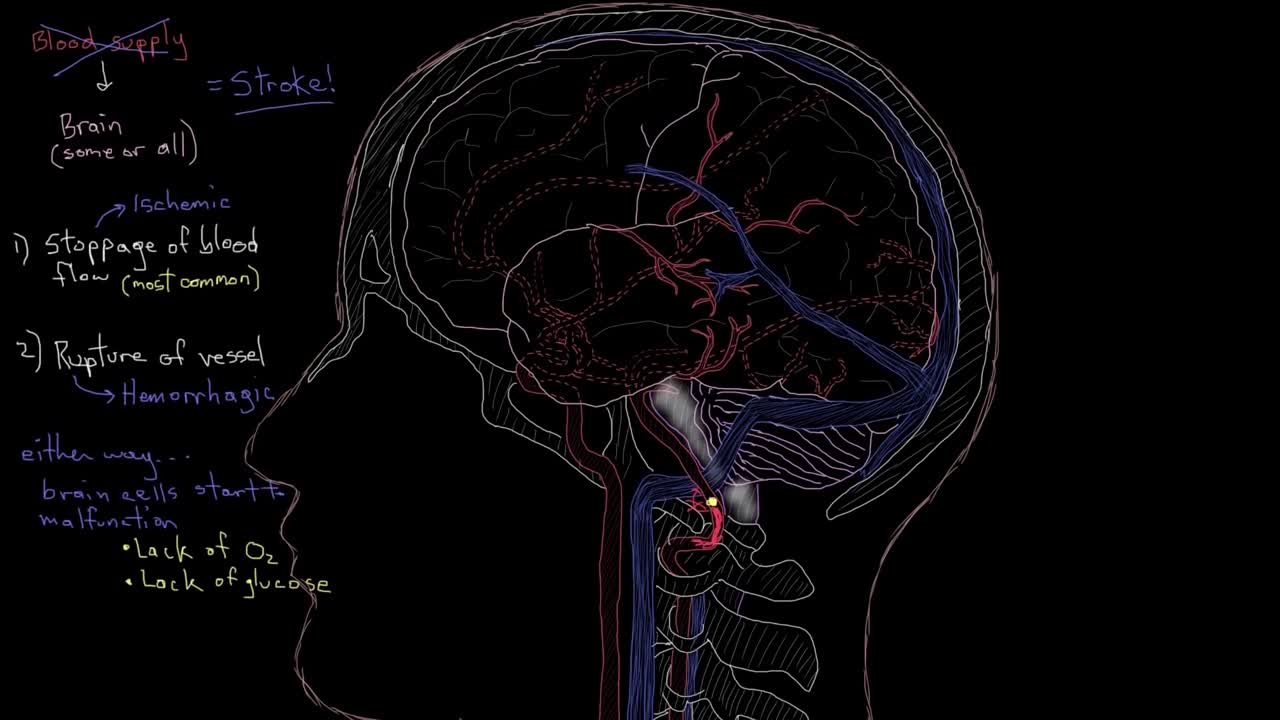

中风患者跟踪治疗调查

中风后大脑结构示意动画(1)

中风后大脑结构示意动画(2)